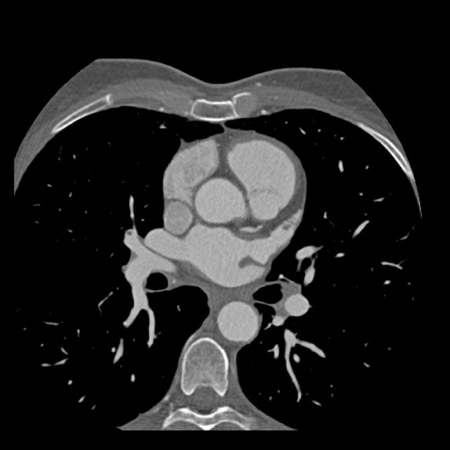

case 1 – CAD-RADS 2/P1

First, scroll through the scan.

Not all images are included. Some images without any abnormalities are skipped

from the series.

How would you describe the findings on the coronary CTA?

The findings are:

- Agatston score of

this patient was 14 (P1). Please, also note the calcification of the aortic valve. - Some partially

calcified and calcified plaques are present in the LAD with mild stenosis

(25-49%). - Calcified-plaque in

the LCX causing minimal stenosis (<25%). - Non-calcified

plaque in the distal RCA causing minimal stenosis (<25%). - This patient classifies

as CAD-RADS 2/P1, which means no further workup is needed.